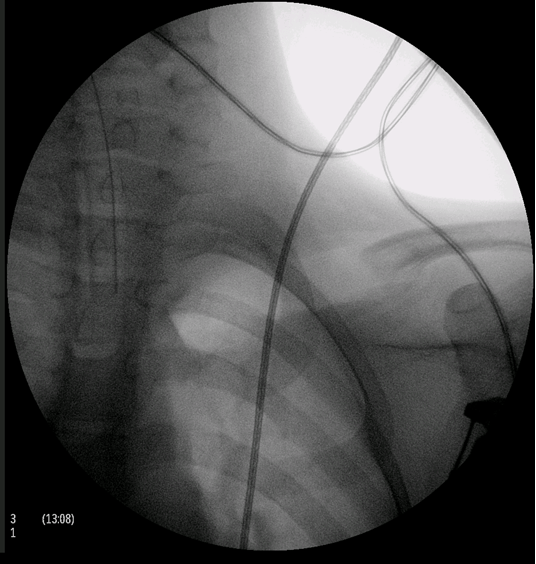

This is a case of an 11-year-old boy with left clavicle pain with two months of evolution presented to emergency department. No history of trauma, fever or systemic signs, recent illness and no relevant personal or familiar medical history. No neurological or vascular abnormalities were found in the upper arms. Left shoulder X-ray revealed a hyperdense lesion and increased thickness of left clavicle (Figure 1). In this context a computed tomography (CT) scan and after a magnetic resonance imaging (MRI) scan were ordered. Both scans demonstrated morphological changes of the median half of the clavicle, cortical destruction and periosteal reaction. Also changes in the surrounding soft and muscular tissue and bulky and numerous locoregional ganglion formations (Figure 2) and (Figure 3). Blood analysis, blood cultures and bone biopsy were negative for infection and neoplastic disorder. In this context, by exclusion, and in the presence of two Jansson major diagnostic criteria (radiologically proven osteolytic/osteosclerotic bone lesions and sterile bone biopsy with signs of inflammation) [1], we reached the diagnosis of chronic recurrent multifocal osteomyelitis (CMRO) (Table 1). Patient was treated with NSAIDs for six months and a short course of corticoids without any response. By keeping complaints of marked and recalcitrant pain in clavicle region, we opted for the surgical treatment: resection of the lesion en bloc, about 7 cm of clavicle (Figure 4), maintaining the integrity of periosteum to allow neo-osteogenesis of the clavicle. No bone grafting or another material was interposed in the dead space left by the resection of the clavicle. Post operatory X-ray, showing a radiopaque area corresponding to the excision of the medial portion of the clavicle (Figure 5).

Figure 3: A coronal T1-weighted magnetic resonance imaging (MRI) scan showing an increased thickness of left clavicle and changes in the surrounding soft and muscular tissue and bulky with numerous locoregional ganglion formations.